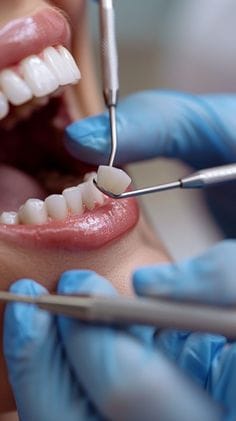

تبييض الأسنان. - قشور الفينير (veneer) لتغطية الأسنان المعيبة.

- إعادة تشكيل وتعديل الأسنان لتحسين المظهر.